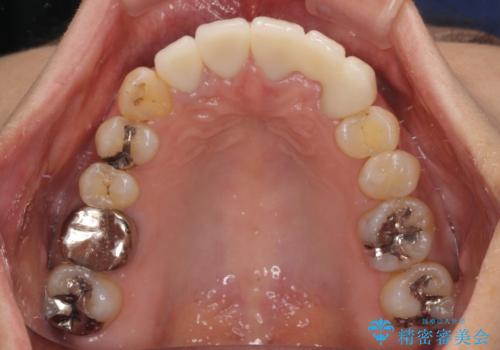

- 非対称な前歯や奥歯の目立つ銀歯を気にして来院された患者様です。

左上前から2番目の歯は、以前裏側に位置していたことから抜歯をされていましたが、前歯の非対称が長年気になっているとのことでした。

矯正治療によって前歯にスペースを作り、左右対称となるようにオールセラミッククラウンにて補綴治療を行うとしました。

他にも奥歯の咬み合わせに問題があったので、全顎的な矯正治療を行い、前歯以外にも口を開けたときに目立つ奥の銀歯をセラミッククラウンにて補綴治療を行うこととしました。